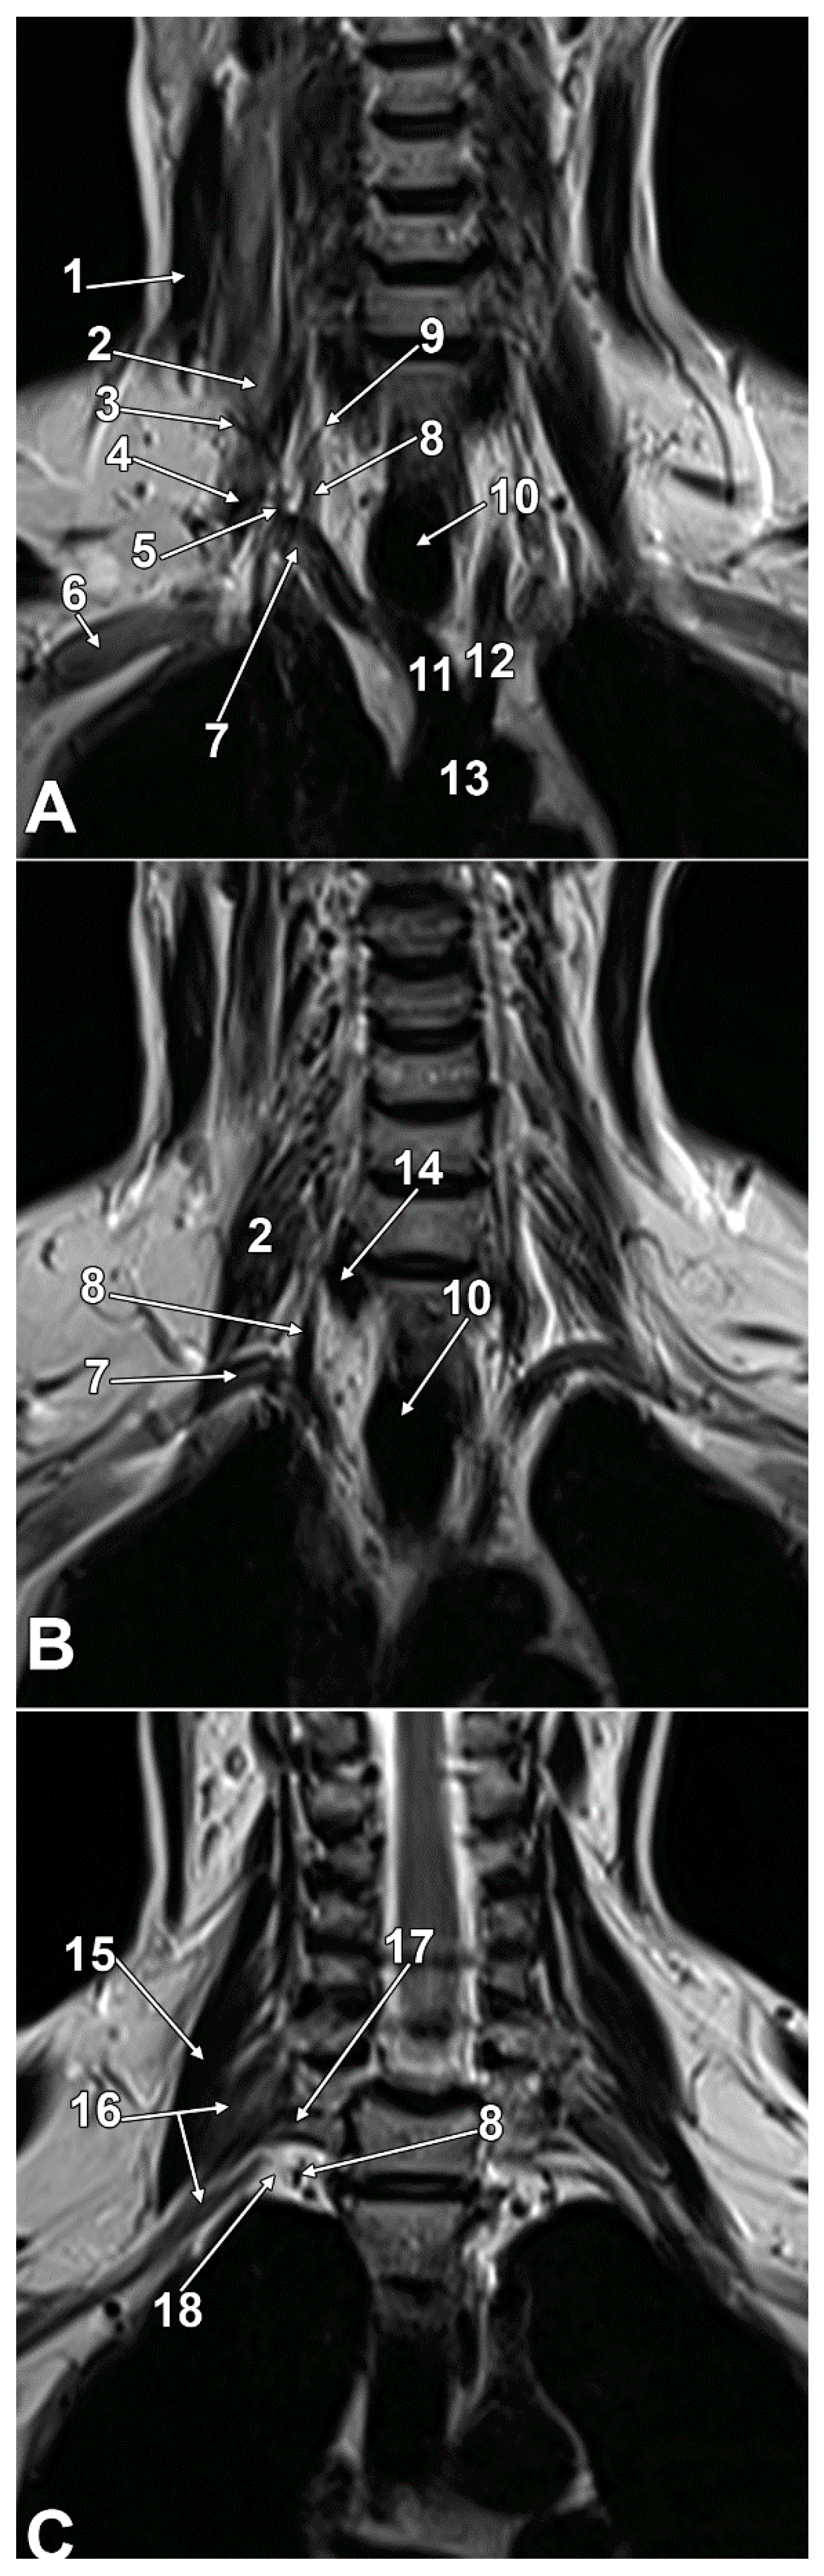

3.4. Imaging Anatomy of the SG